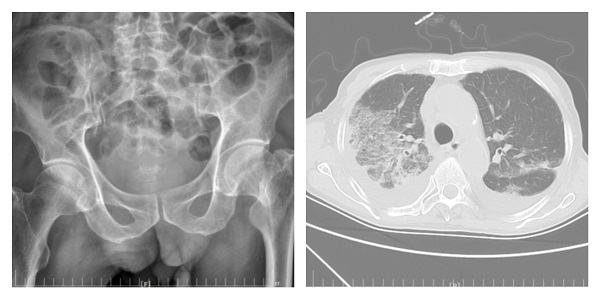

许爷爷今年83岁,不慎摔伤致左髋部疼痛入住陕健医二一五医院骨五科,完善检查发现许爷爷新冠病毒检测为阳性,肺部已有感染。由于年事已高,有基础病且合并新冠病毒感染,病情复杂危重,情况非常棘手。骨五科潘建宏主任团队为许爷爷进行了全面细致的病情评估,并请院内相关专家组会诊,制定了有针对性的治疗方案。